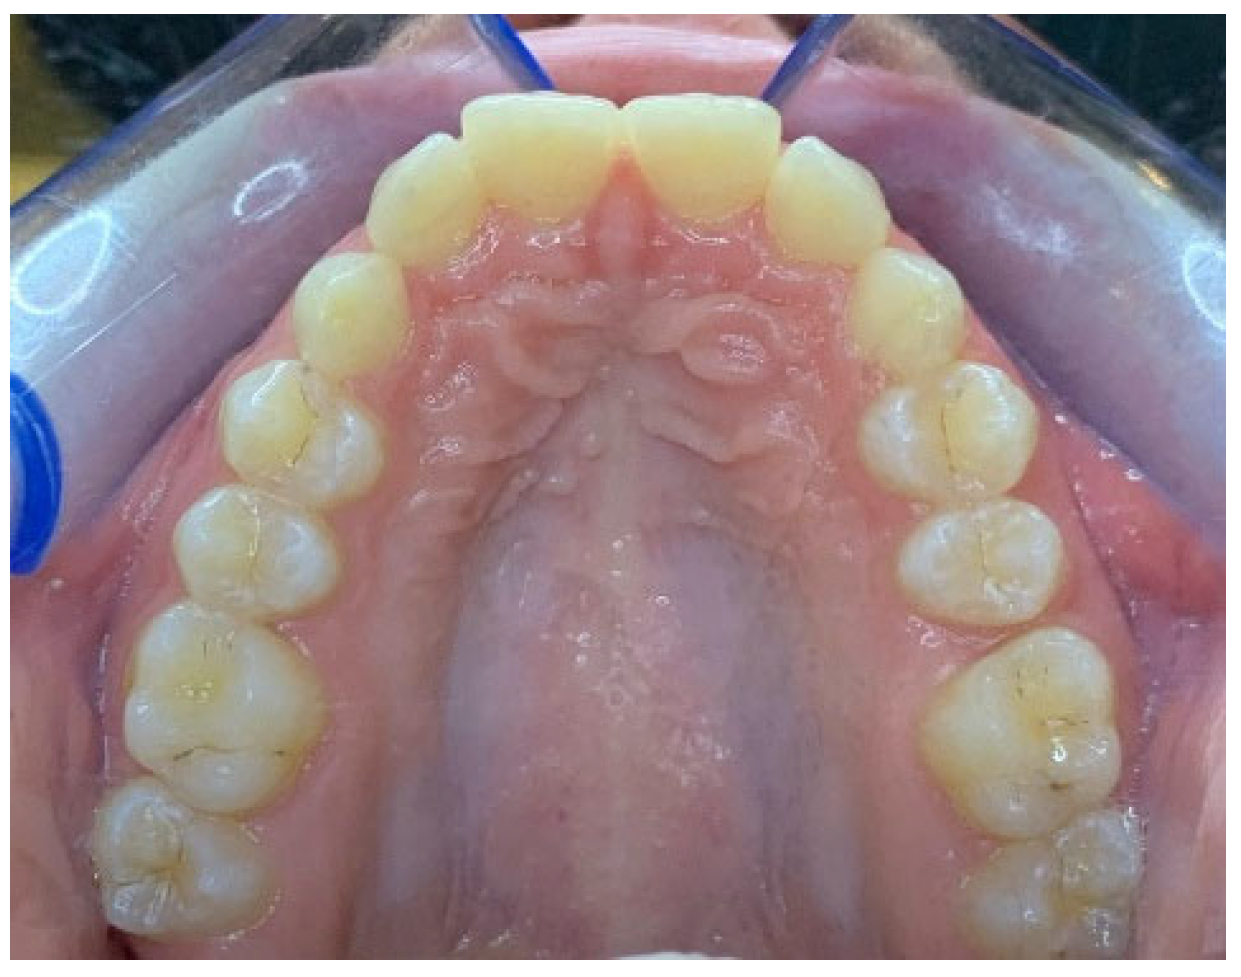

Check-up appointments after surgery were organized as follows: one week (T1), four weeks (T2), eight weeks (T3), and sixteen weeks (T4) (Figure 5).

During each control, a clinical evaluation was carried out and intraoral photos of canine eruption were taken. Intraoral scans were performed to monitor the eruption movements of the canines at T4. At T1 the periodontal patch was removed, and the patient did not report pain, discomfort, or the necessity to take painkillers.

At the end of the monitoring time of 16 weeks, at T4, the inclusion height of element 1.3 was 7.00 mm and of element 2.3 was 3.76 mm. This means that the canines erupted to an extent of 0.21 mm and 3.16 mm, respectively.

Figure 5. Intraoral occlusal photo of the patient 16 weeks after surgery.